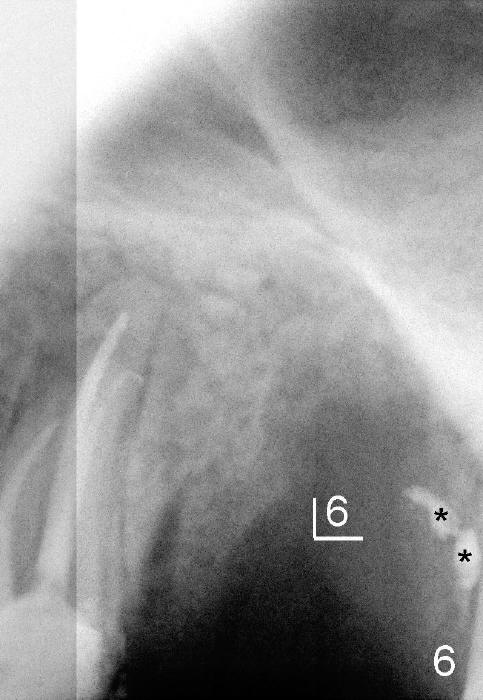

上颌第一前臼齿一般有两个根管(颊侧,鄂侧),偶尔上颌前臼齿有三个根管,可发生于第一或者第二(本例),病人二十四岁,黑人,男,左上第二前臼齿(图一:5)髓腔(*)好像分成三个根管(箭头),仔细观察显示根尖也有三个(图二(图一放大)彩色轮廓与第一磨牙三个根对比:近中颊侧(MB),远中颊侧(DB),鄂侧(P))。因此有三个根管的前臼齿好像小型磨牙,不过颊侧两个根融合。

开髓时发现颊侧(图三B)髓腔比鄂侧(P)宽,根管口分布与上颌磨牙不差上下(图四),图三图四是镜影像。图五显示根管充填后:三个牙胶尖;AH26 Plus 糊剂超填(*),基本在第一磨牙牙槽窝(6)近中,第一磨牙两个月前拔除。根管治疗完成后九天糊剂(图六*)转移到第一磨牙牙槽窝远中,说明牙槽骨象蜂窝,糊剂,细菌自由来往,植牙周围不应该有感染。